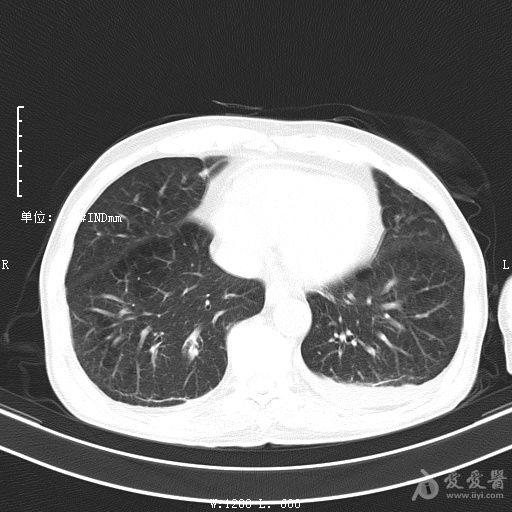

最新的肺炎疫情形勢嚴峻,病毒變異使得防控工作更加復(fù)雜,許多地方出現(xiàn)了新的病例,甚至有些地區(qū)的疫情出現(xiàn)了反彈,這不僅是對醫(yī)療系統(tǒng)的考驗,更是對每一個生命的考驗,我們需要密切關(guān)注疫情動態(tài),共同應(yīng)對這場挑戰(zhàn)。??